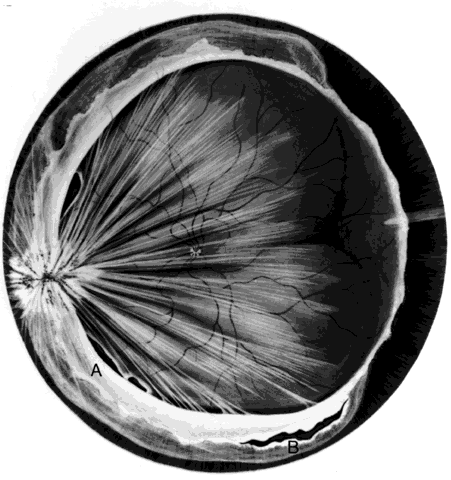

Retinal breaks are created at the time of nonpenetrating blunt injuries3 in 10% to 20% of eyes.3–6 Retinal dialyses are most frequent2–6 and are most often found in the lower temporal (Fig. 2) and upper nasal periphery (Fig. 3).2 Large irregular breaks at the point of impact of blunt trauma are less common but are equally characteristic of nonpenetrating injuries (see Fig. 3).2,7,8 Horseshoe and opercular tears of the equatorial retina (see Fig. 3) are associated with the more characteristic breaks in 25% of eyes.2 Small round holes in atrophic retina at the point of traumatic impact and macular holes (see Fig. 3) are infrequently observed after ocular contusion.2,8

Fig. 2. Large lower temporal dialysis at the point of impact of blunt trauma. (Cox MS: Retinal breaks caused by blunt nonperforating trauma at the point of impact. Trans Am Ophthalmol Soc 78:418, 1980)

Retinal dialyses in the lower temporal quadrant are often very large, with gaping posterior edges located well behind the equator (see Fig. 2). They are caused by injuries impacting the lower temporal portion of the globe that result in the dissolution and disappearance of retinal tissue.8 In contrast to nontraumatic giant retinal tears with rolled-over retina, they respond favorably to scleral buckling without vitrectomy. A scleral buckle is indicated for smaller dialyses that can be closed with an explant of reasonable size. Very large breaks, as illustrated in Figure 2, are best treated with vitrectomy, gas tamponade, and laser, as recommended for nontraumatic giant retinal tears, rather than with a very large scleral buckle.